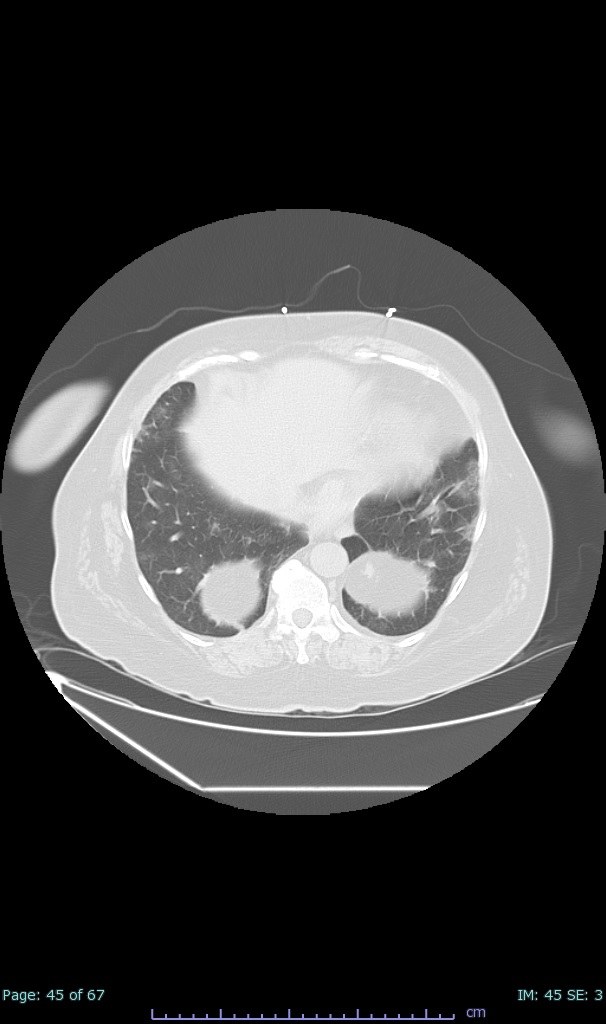

- 100% subpleural involvement, 33% + centrolobular involvement

- 40% even apical/basilar, 27% basilar dom, 5% mid dom. 1/17